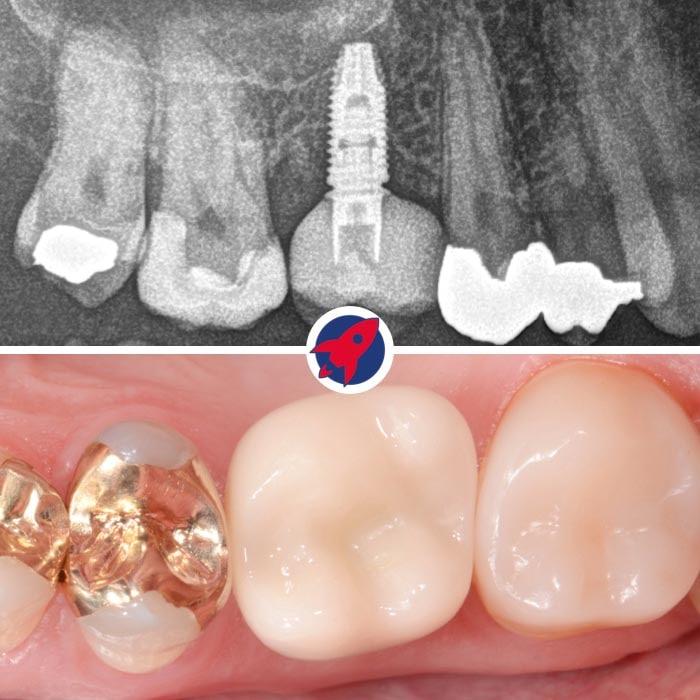

Oben sehen Sie ein Röntgenbild, das das Implantat mit aufgesetzter Zahnkrone zeigt. Unten ist die Krone in der klinischen Ansicht im Mund dargestellt.

Endgültige Ansicht eines Zahnimplantats mit Krone: Hier ist das finale Ergebnis einer Implantatbehandlung zu sehen, bei dem das Implantat vollständig im Kiefer integriert ist und mit einer individuell angefertigten Zahnkrone abgeschlossen wird, die sich nahtlos in die natürliche Zahnreihe einfügt.

Wir geben Ihnen die Sicherheit, dass Ihr Ergebnis nicht nur schön aussieht, sondern stabil ist und viele Jahre hält. Dies sind exklusive Beispiele aus unserer Praxis in Jestetten (20 Minuten von Zürich):

Echte Beispiele aus unserer Praxis

Zahnimplantat-Behandlungen im Vorher-Nachher-Vergleich